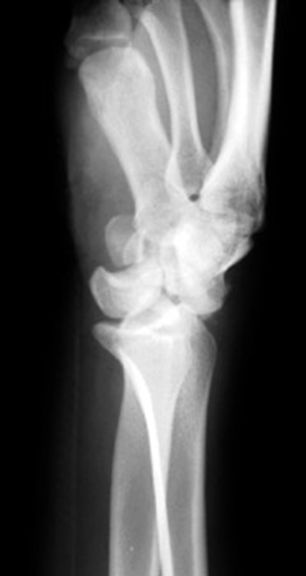

Colles骨折

• 桡骨远端骨折

• 骨折向掌侧成角

• 远折端向背侧移位